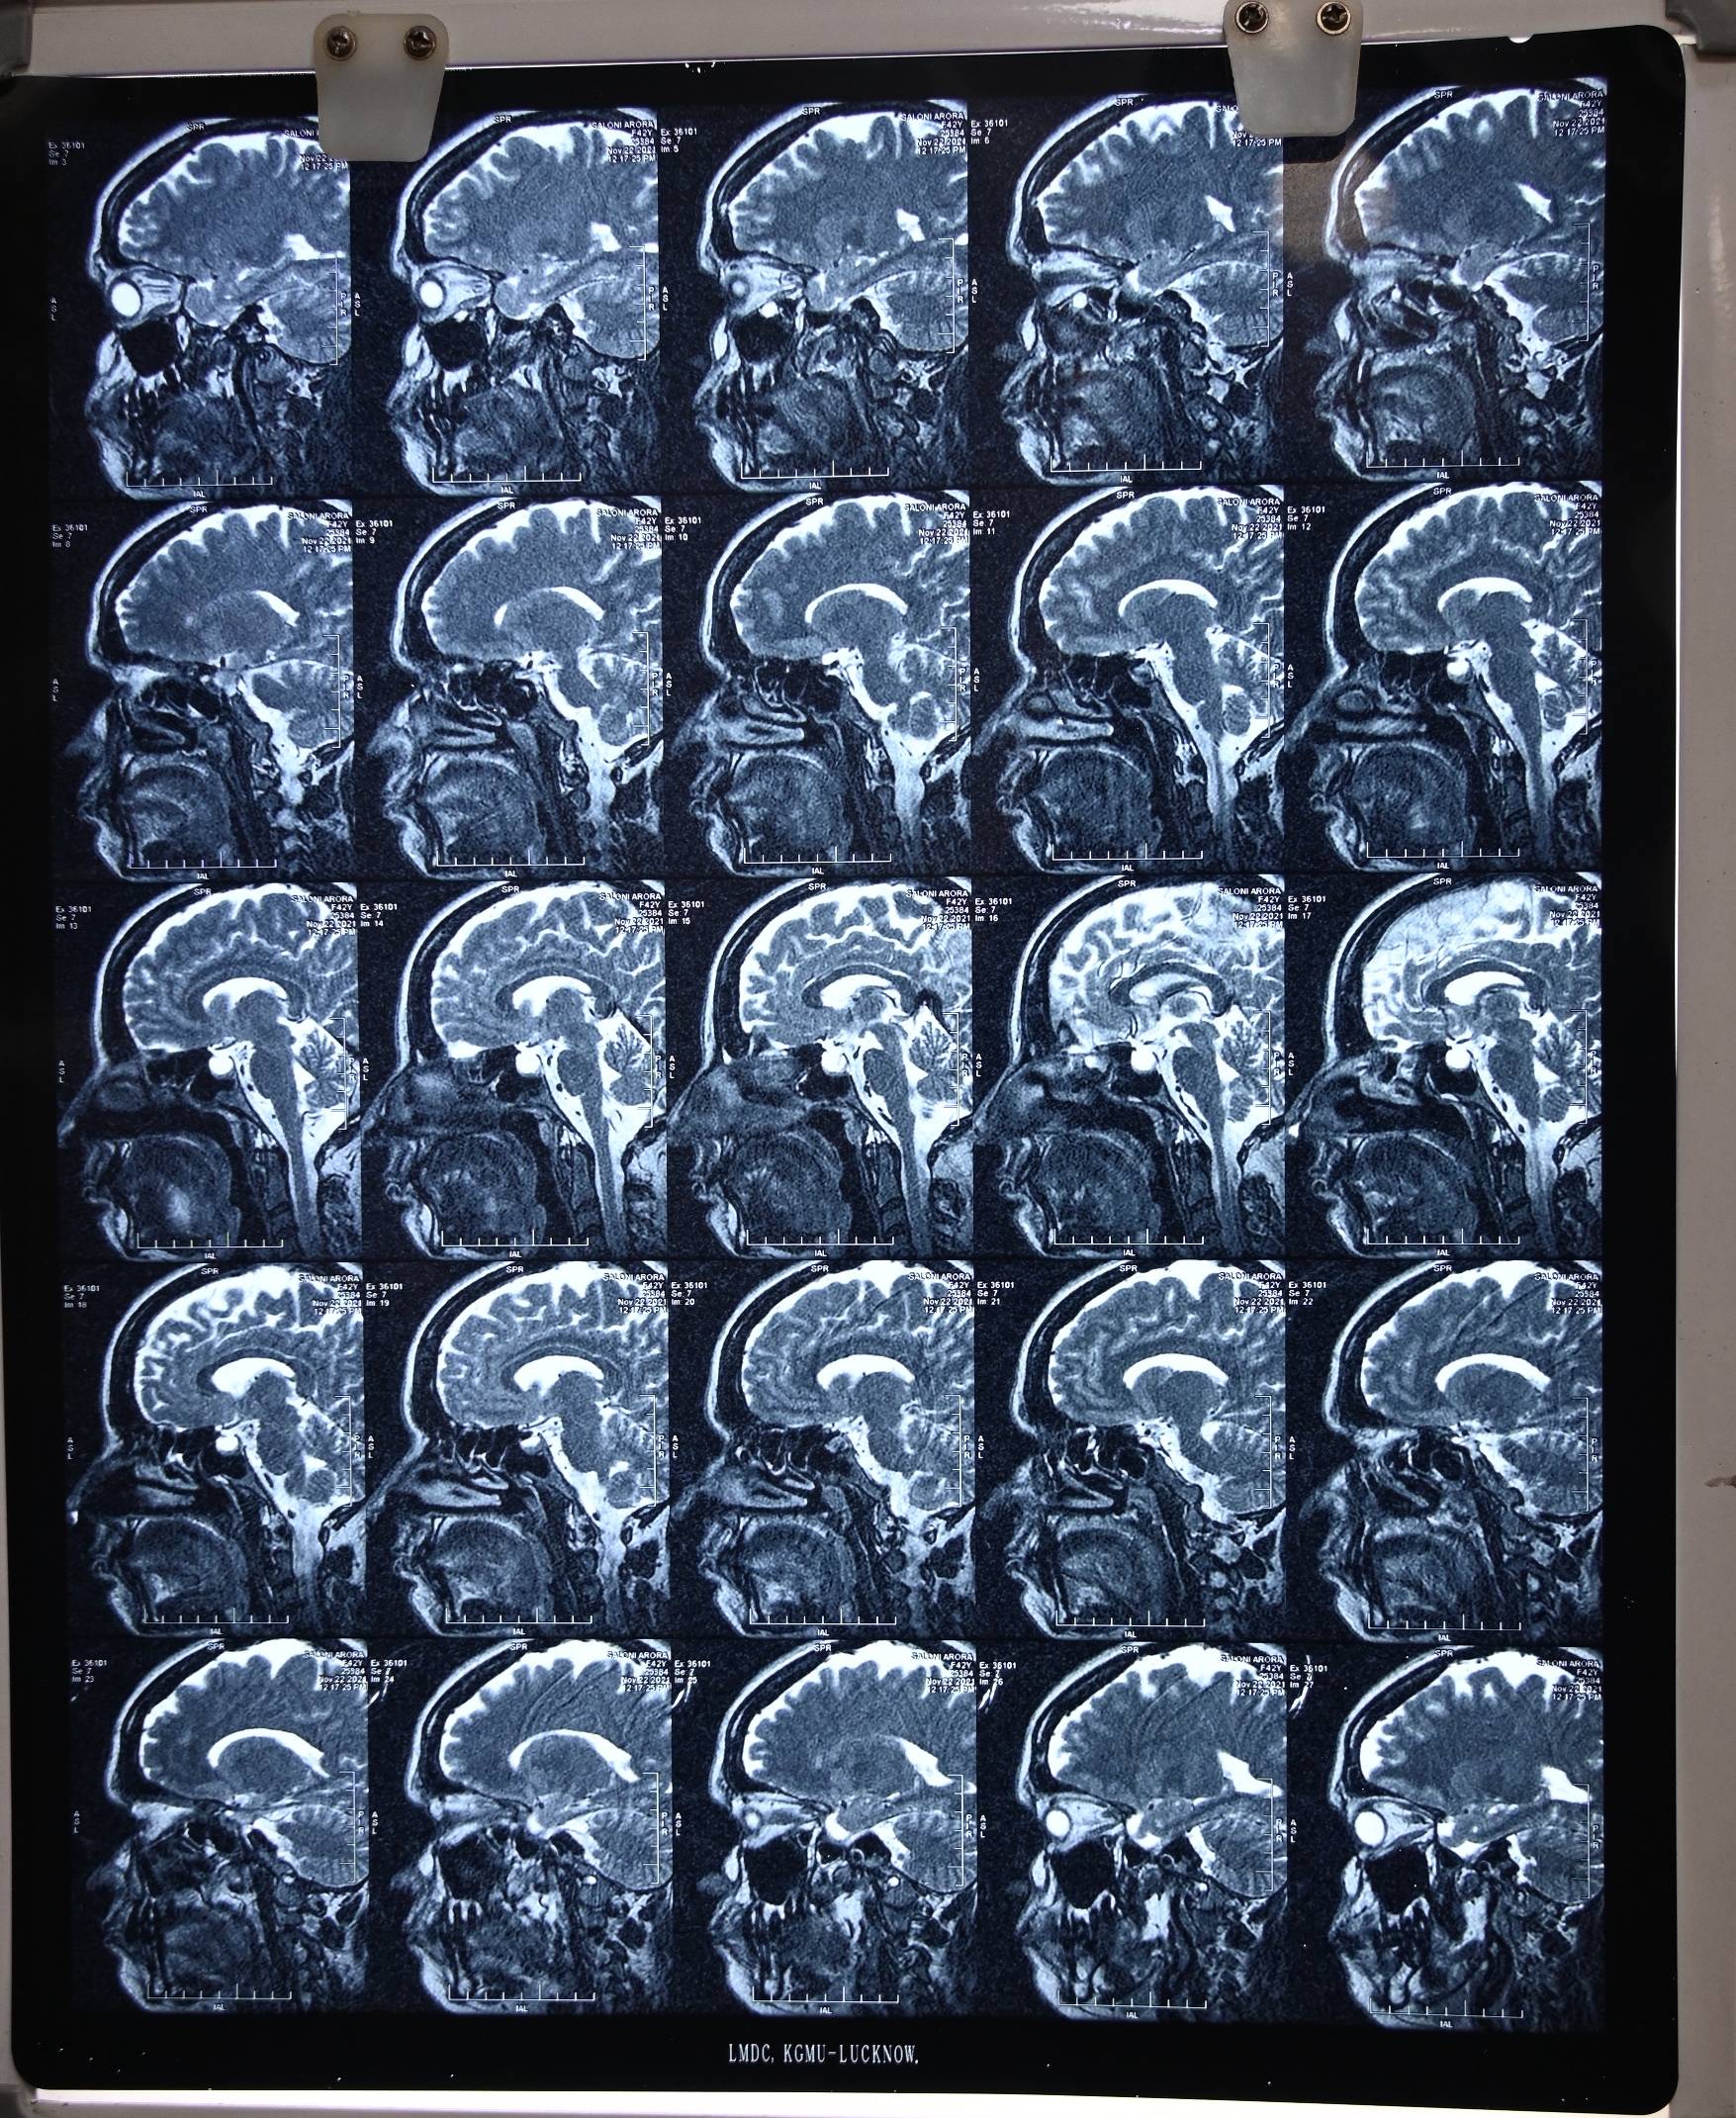

There is no Csf leak for many months. She got advised to undergo CT cisternography to rule out any remaining defect.

She awas again advised for the Ct cisternography but our of fear or anxiety she is postponing the investigation, which is crucial in determining the cure.

Dr Ravi talked with patient over the zoom call on 18th March 2024. She got cured for her CSF Rhinorrhea trouble. For last 10 months she never experienced any single drop of CSF leak. She got advised for its prognostic lab test CT cisternography, but she is constantly making some excuses for the same. Her migraine trouble also got cured.